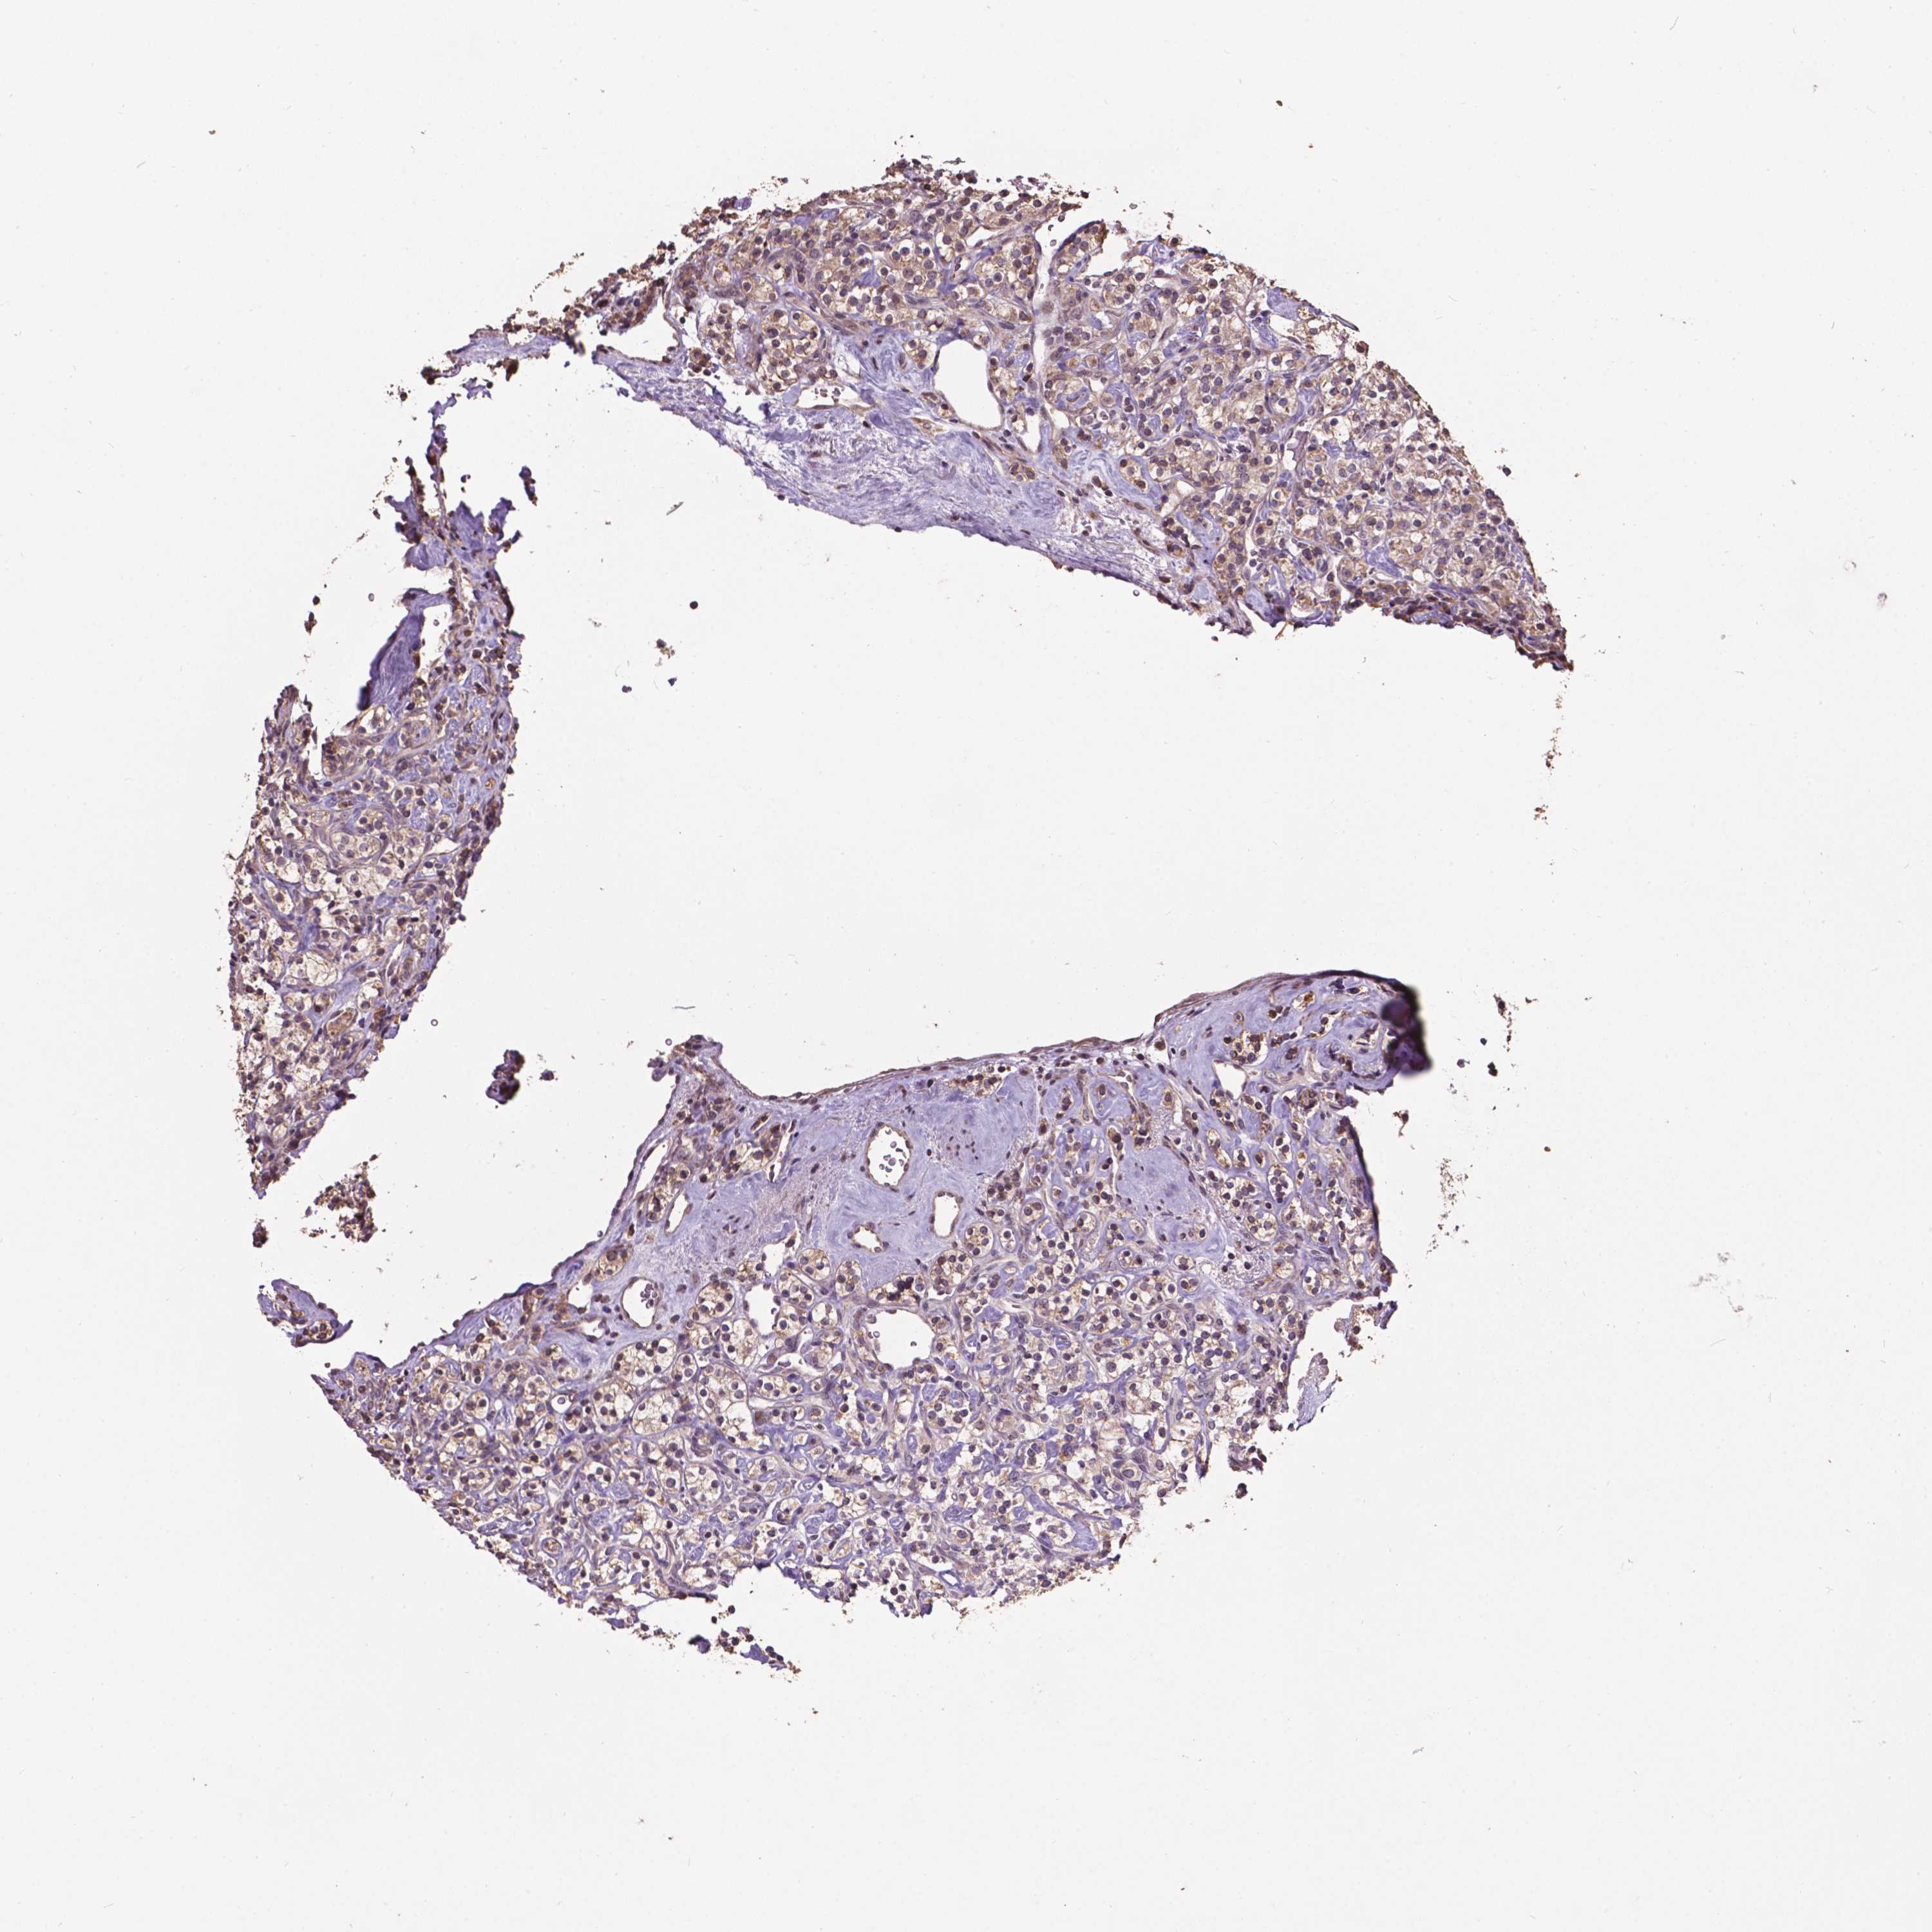

KIDNEY RENAL CLEAR CELL CARCINOMA (VALIDATION) - Interactive survival scatter ploti

The Survival Scatter plot shows the clinical status (i.e. dead or alive) for all individuals in the patient cohort, based on the same data that underlies the corresponding Kaplan-Meier plots. Patients that are alive at last time for follow-up are shown in blue and patients who have died during the study are shown in red.

The x-axis shows the expression levels (FPKM) of the investigated gene in the tumor tissue at the time of diagnosis. The y-axis shows the follow-up time after diagnosis (years). Both axes are complimented with kernel density curves demonstrating the data density over the axes. The top density plot shows the expression levels (FPKM) distribution among dead (red) and alive patients (blue). The right density plot shows the data density of the survived years of dead patients with high and low expression levels respectively, stratified using the cutoff indicated by the vertical dashed line through the Survival Scatter plot. This cutoff is automatically defined based on the FPKM cutoff that minimizes the p-score. The cutoff can be changed by dragging the vertical line or by entering a cutoff value in the square labeled "Current cut-off".

Under the Survival Scatter plot the p-score landscape (black curve; left axis) is shown together with dead median separation (red curve; right axis). Dead median separation is the difference in median mRNA expression between patients who have died with high and low expression, respectively. It is calculated as follows: median FPKM expression of dead patients with high expression - median FPKM expression of dead patients with low expression. This is intended to aid the user in visually exploring custom cutoffs and the associated p-scores and dead median separation.

Individual patient data is displayed and can be filtered by clicking on one or more of the category buttons on the top of the page. Categories describing expression level and patient information include: high, low, alive, dead, female, male and tumor stages. The scale of the x-axis can be toggled between linear and log-scale by clicking on the "x log" button. Mouse-over function shows TCGA ID, patient information and mRNA expression (FPKM) for each patient.

& Survival analysisi

Kaplan-Meier plots summarize results from analysis of correlation between mRNA expression level and patient survival. Patients were divided based on level of expression into one of the two groups "low" (under cut off) or "high" (over cut off). X-axis shows time for survival (years) and y-axis shows the probability of survival, where 1.0 corresponds to 100 percent.

GLRA2 is not prognostic in Kidney Renal Clear Cell Carcinoma (validation)

TCGA RNA samplesi

RNA-seq data is reported as average FPKM (number Fragments Per Kilobase of exon per Million reads), generated by the The Cancer Genome Atlas (TCGA) .

Normal distribution across the dataset is visualized with box plots, shown as median and 25th and 75th percentiles. Points are displayed as outliers if they are above or below 1.5 times the interquartile range. FPKM values of the individual samples are presented next to the box plot.

Average pTPM 0.0

Number of samples 100